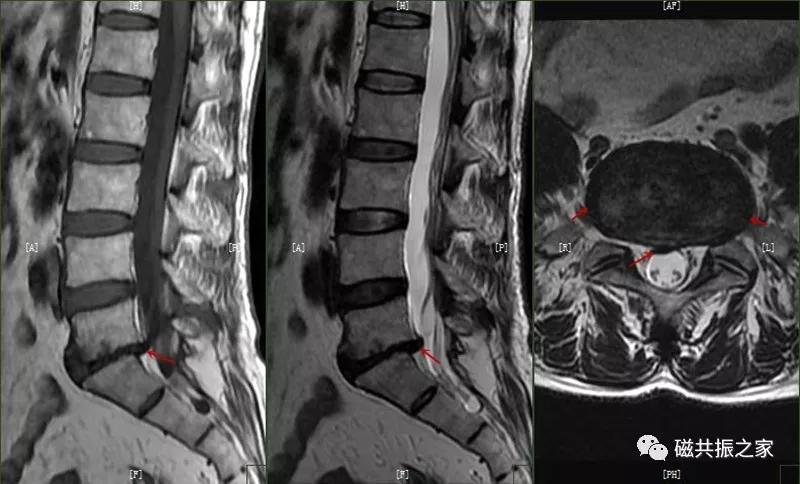

许莫尔结节(Schmorl,snodes),是休门病的一个病例征象。1930年Schmorl对照检查8000例尸检和X线发现椎体生长板发育不完善,或后天外伤致椎间盘突入椎体骨松质内,形成椎体压迹,是休门病的主要征象之一。除休门病外,其他的原因引起的生长板破坏,也可能产生Schmorl结节样改变。

矢状面显示椎体上或下椎间盘面异常信号,常呈长T,长T2信号,见髓核信号突入椎体内,常伴椎间隙变窄,常见于L3~S1椎体。

椎体边缘骨,类似于Schmorl改变,一类是椎体生长板和椎体二次骨化中心软骨发育异常,致其不能完全愈合,造成的椎间盘疝入其间,形成边缘体的椎体边缘骨。

椎体生长板和椎体二次骨化中心软骨发育异常,致其不能完全愈合,造成的椎间盘疝入其间,形成边缘体的椎体边缘骨。

另一类是椎体后缘骨内软骨结节,椎间盘疝入骨内,形成椎体后缘的Schmorl结节样改变,椎体终板及髓核等突入其中,椎体骨质增生,常见于L4、L5椎体下缘。

椎体后缘骨内软骨结节,椎间盘疝入骨内,形成椎体后缘的Schmorl结节样改变,椎体终板及髓核等突入其中,椎体骨质增生,常见于L4、L5椎体下缘。